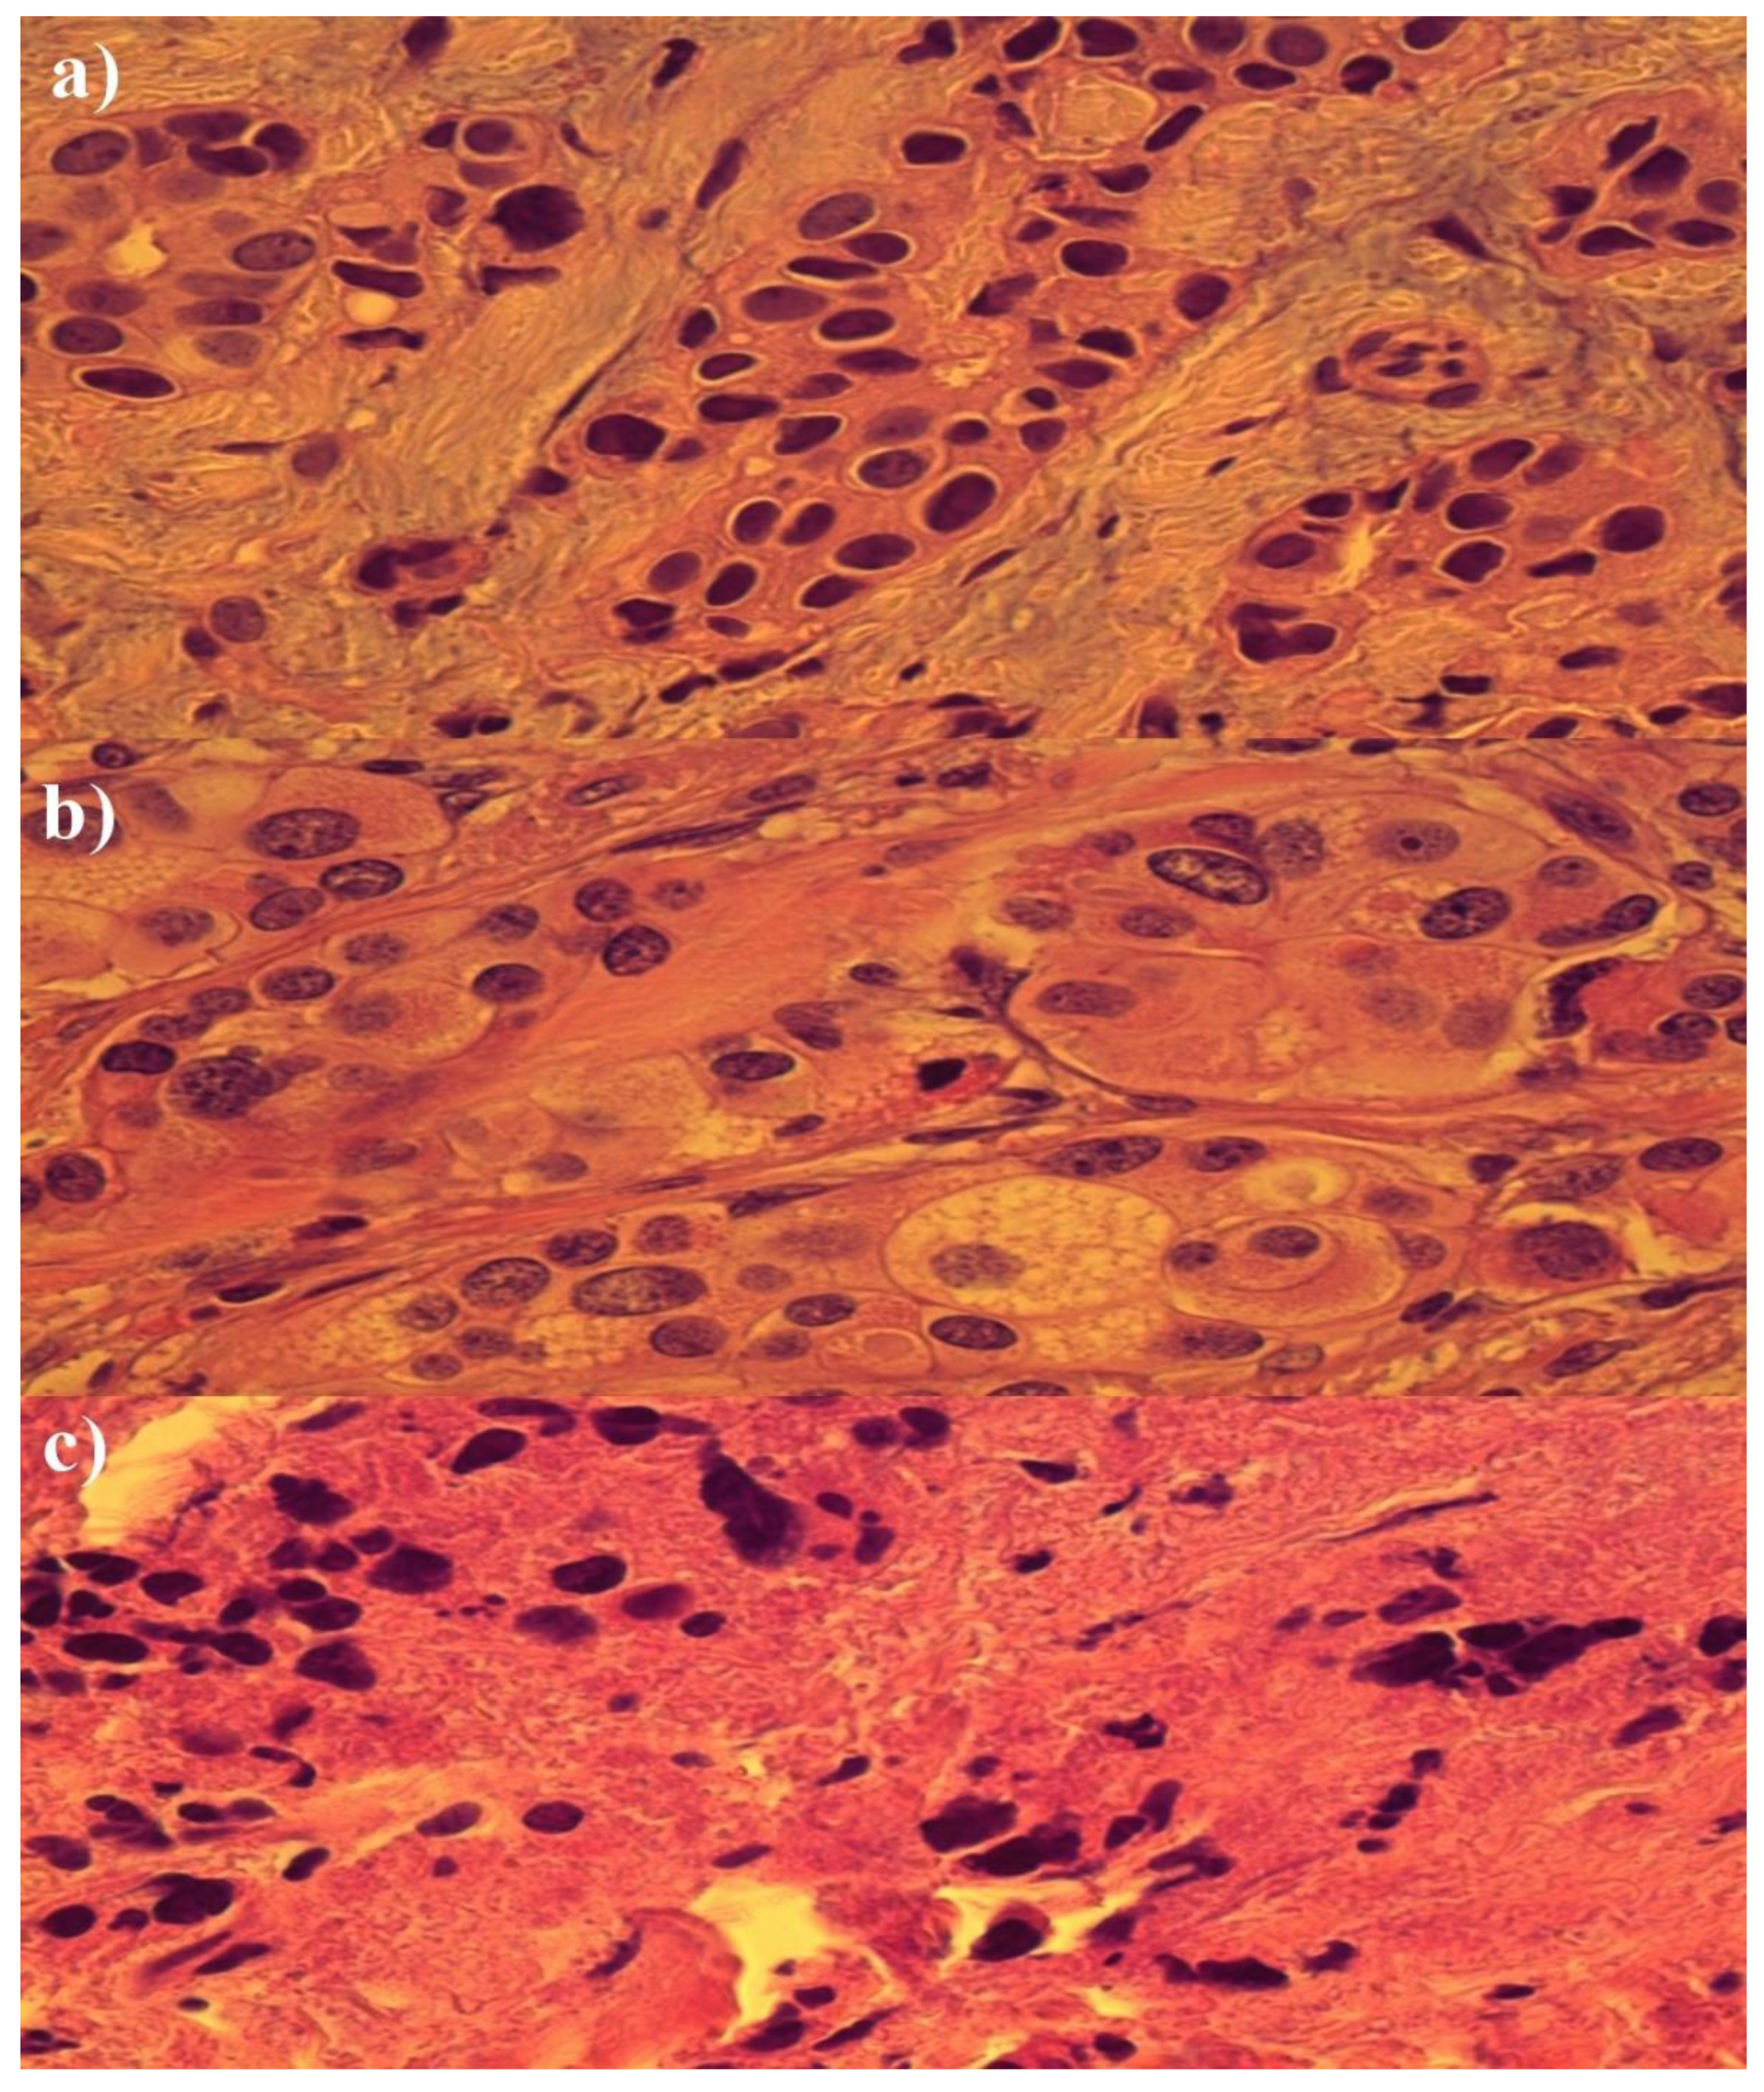

Histopathological Analysis of the Effect of Photodynamic Action on Post-Chemotherapy Excised Breast Cancer Tissue

3. Results